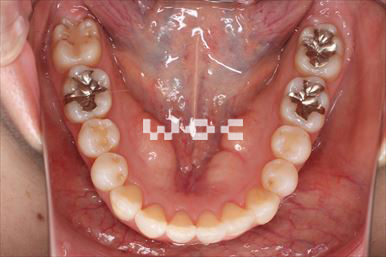

八重歯・叢生上のみ舌側矯正、下はエッジワイズ装置

上は舌側矯正を希望。ガタガタ(叢生)が強い。上顎右側中切歯・側切歯が歯科治療で連結してあったがそれを除去してから治療開始しました。

- 年齢:23歳女性

- 主訴:上下前歯のガタガタが気になる

- 基本矯正料金:103万円

- 治療期間:2年2ヶ月

- 非抜歯